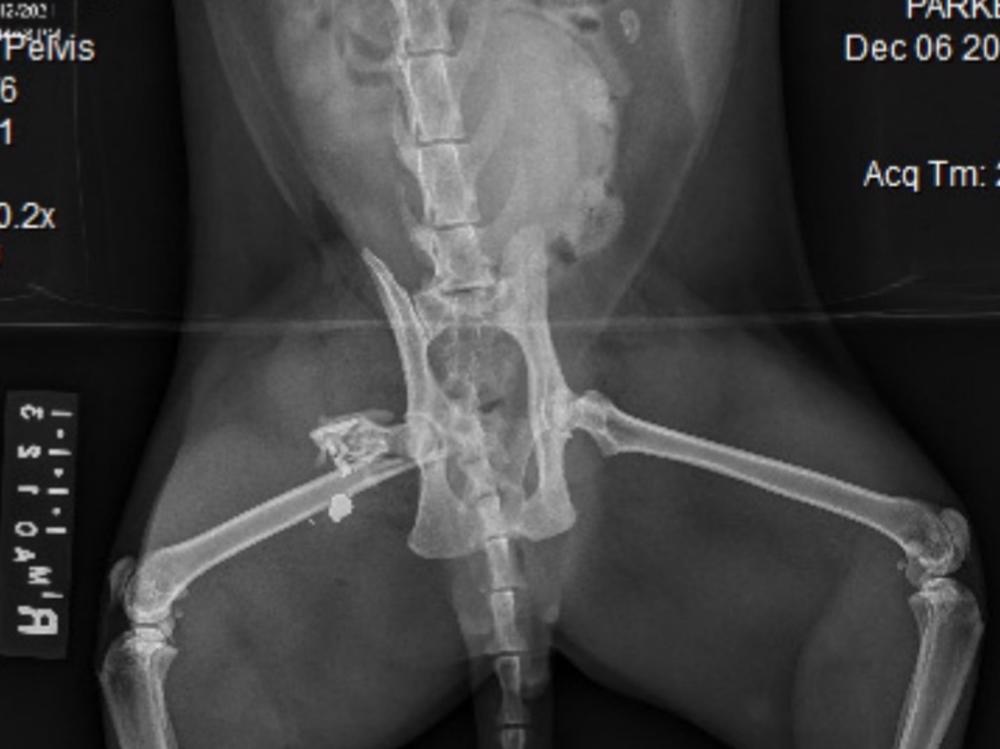

Our Cat Was Shot, Leg Amputated

On the weekend our beautiful ginger boy Rupert was shot in the stomach which resulted in the bullet lodging in his leg shattering his femur beyond repair which meant he's had to go through surgery to amputate his leg. Vet bills are around $2000 currently with the potential to rise so we would be extremely grateful for some support, especially given the fact my wife is due to give birth any day now. SPCA and police are investigating as 3 other cats have been shot aswell, see SPCA NZ Facebook for verification